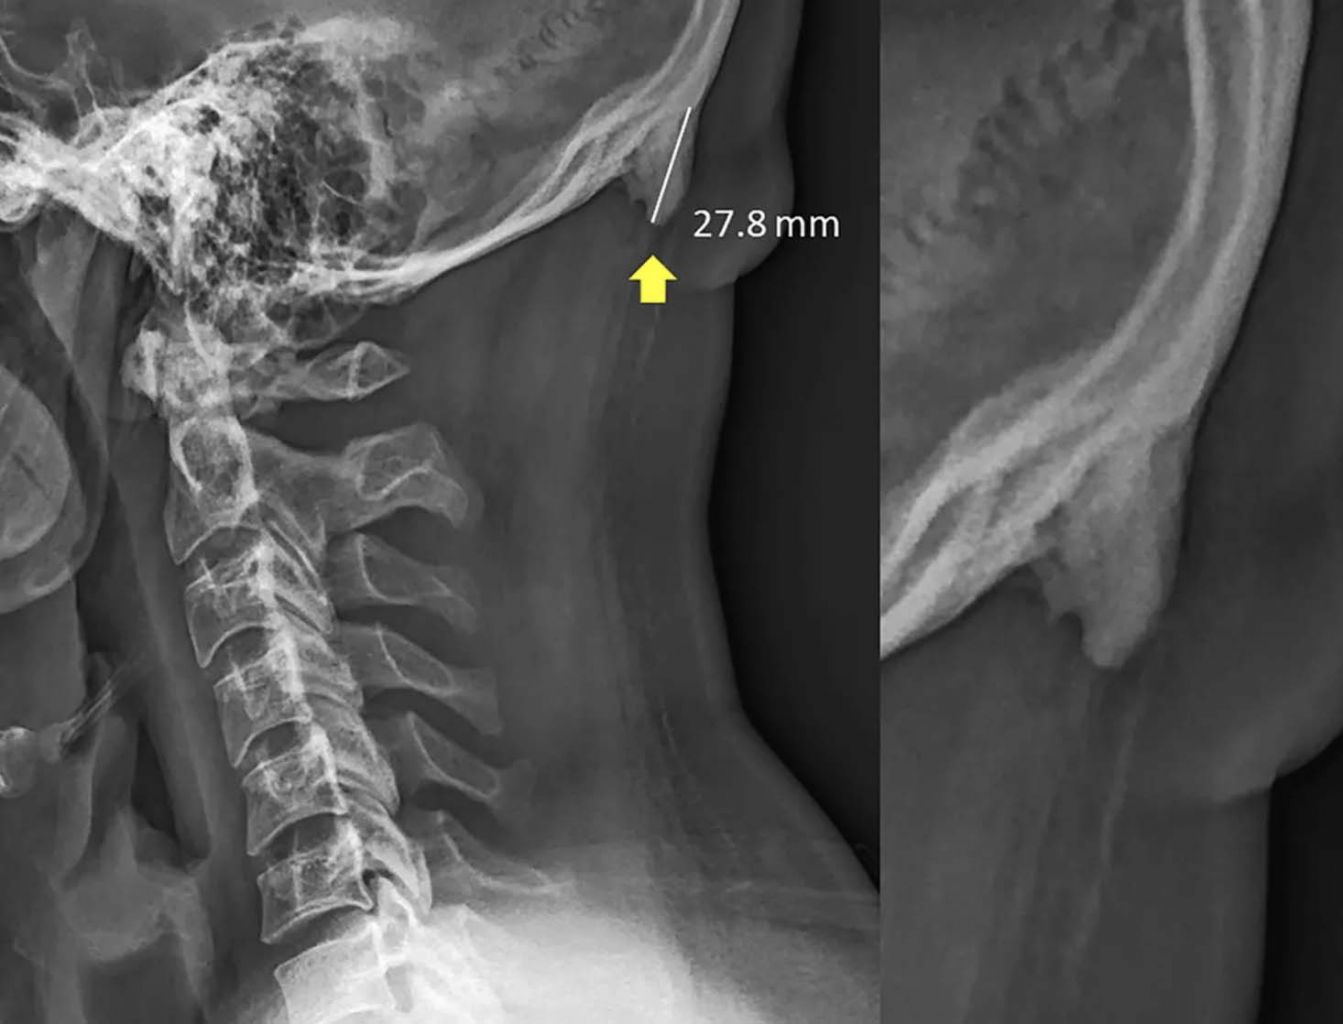

Australian researchers have documented the prevalence of bone spurs at the back of the skull among young adults.

PHOTO: WASHINGTON POST/SCIENTIFIC REPORTS

Part of what was striking about their findings, he said, was the size of the bone spurs, which are thought to be large if they measure 3mm or 5mm in length. An outgrowth was factored into their research only if it measured 10mm.

Their work began about three years ago with a pile of neck X-rays taken in Queensland. The images captured part of the skull, including the area where the bony projections, called enthesophytes, form at the back of the head.

Contrary to conventional understanding of the hornlike structures, which have been thought to crop up rarely and mainly among older people suffering from prolonged strain, Dr Shahar noticed that they appeared prominently on X-rays of younger subjects, including those who were showing no obvious symptoms.

The pair's first paper, published in the Journal of Anatomy in 2016, enlisted a sample of 218 X-rays of subjects aged 18 to 30, to suggest that the bone growth could be observed in 41 per cent of young adults, much more than previously thought.